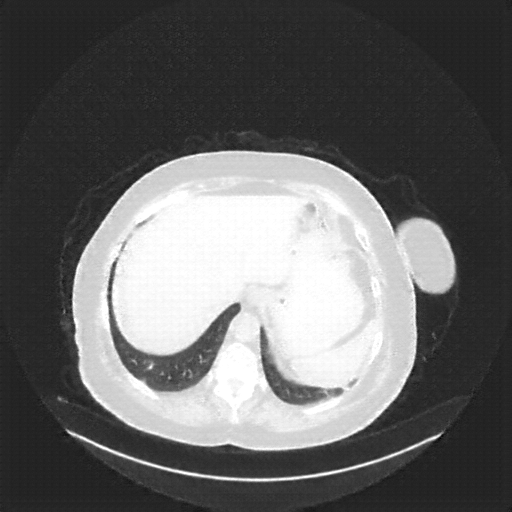

Image Grid

4Γ—3 grid: Rows show different image types (Original NATIVE, Reconstructed NATIVE, Original VENOUS, Generated VENOUS), Columns show windowing techniques (No Window, Lung Window, Mediastinum Window)

Original VENOUS CT scan

Full window (WL 1023.5, WW 4095 β†’ Low βˆ’1024, High +3071)

Lung window (WL -600, WW 1500 β†’ Low βˆ’1350, High +150)